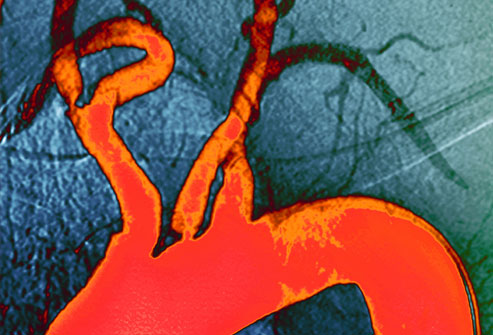

胆固醇水平

高胆固醇会导致能够阻塞动脉血管的斑块(橙色部分)。在斑块形成的很多年中你可能不会出现任何症状,并最终导致心脏病或中风。高血压、糖尿病和吸烟都会引起斑块淤积。斑块淤积被称为动脉粥样硬化。改变生活方式和药物治疗可以降低你的风险。

检查你的胆固醇

检查胆固醇水平,首先你需要禁食12小时。然后血液检查会检查你的总胆固醇水平、LDL胆固醇水平、HDL胆固醇水平、和甘油三酸酯水平(血脂)。如果你的年龄达到了20岁以上,你应该每五年进行一次检查。